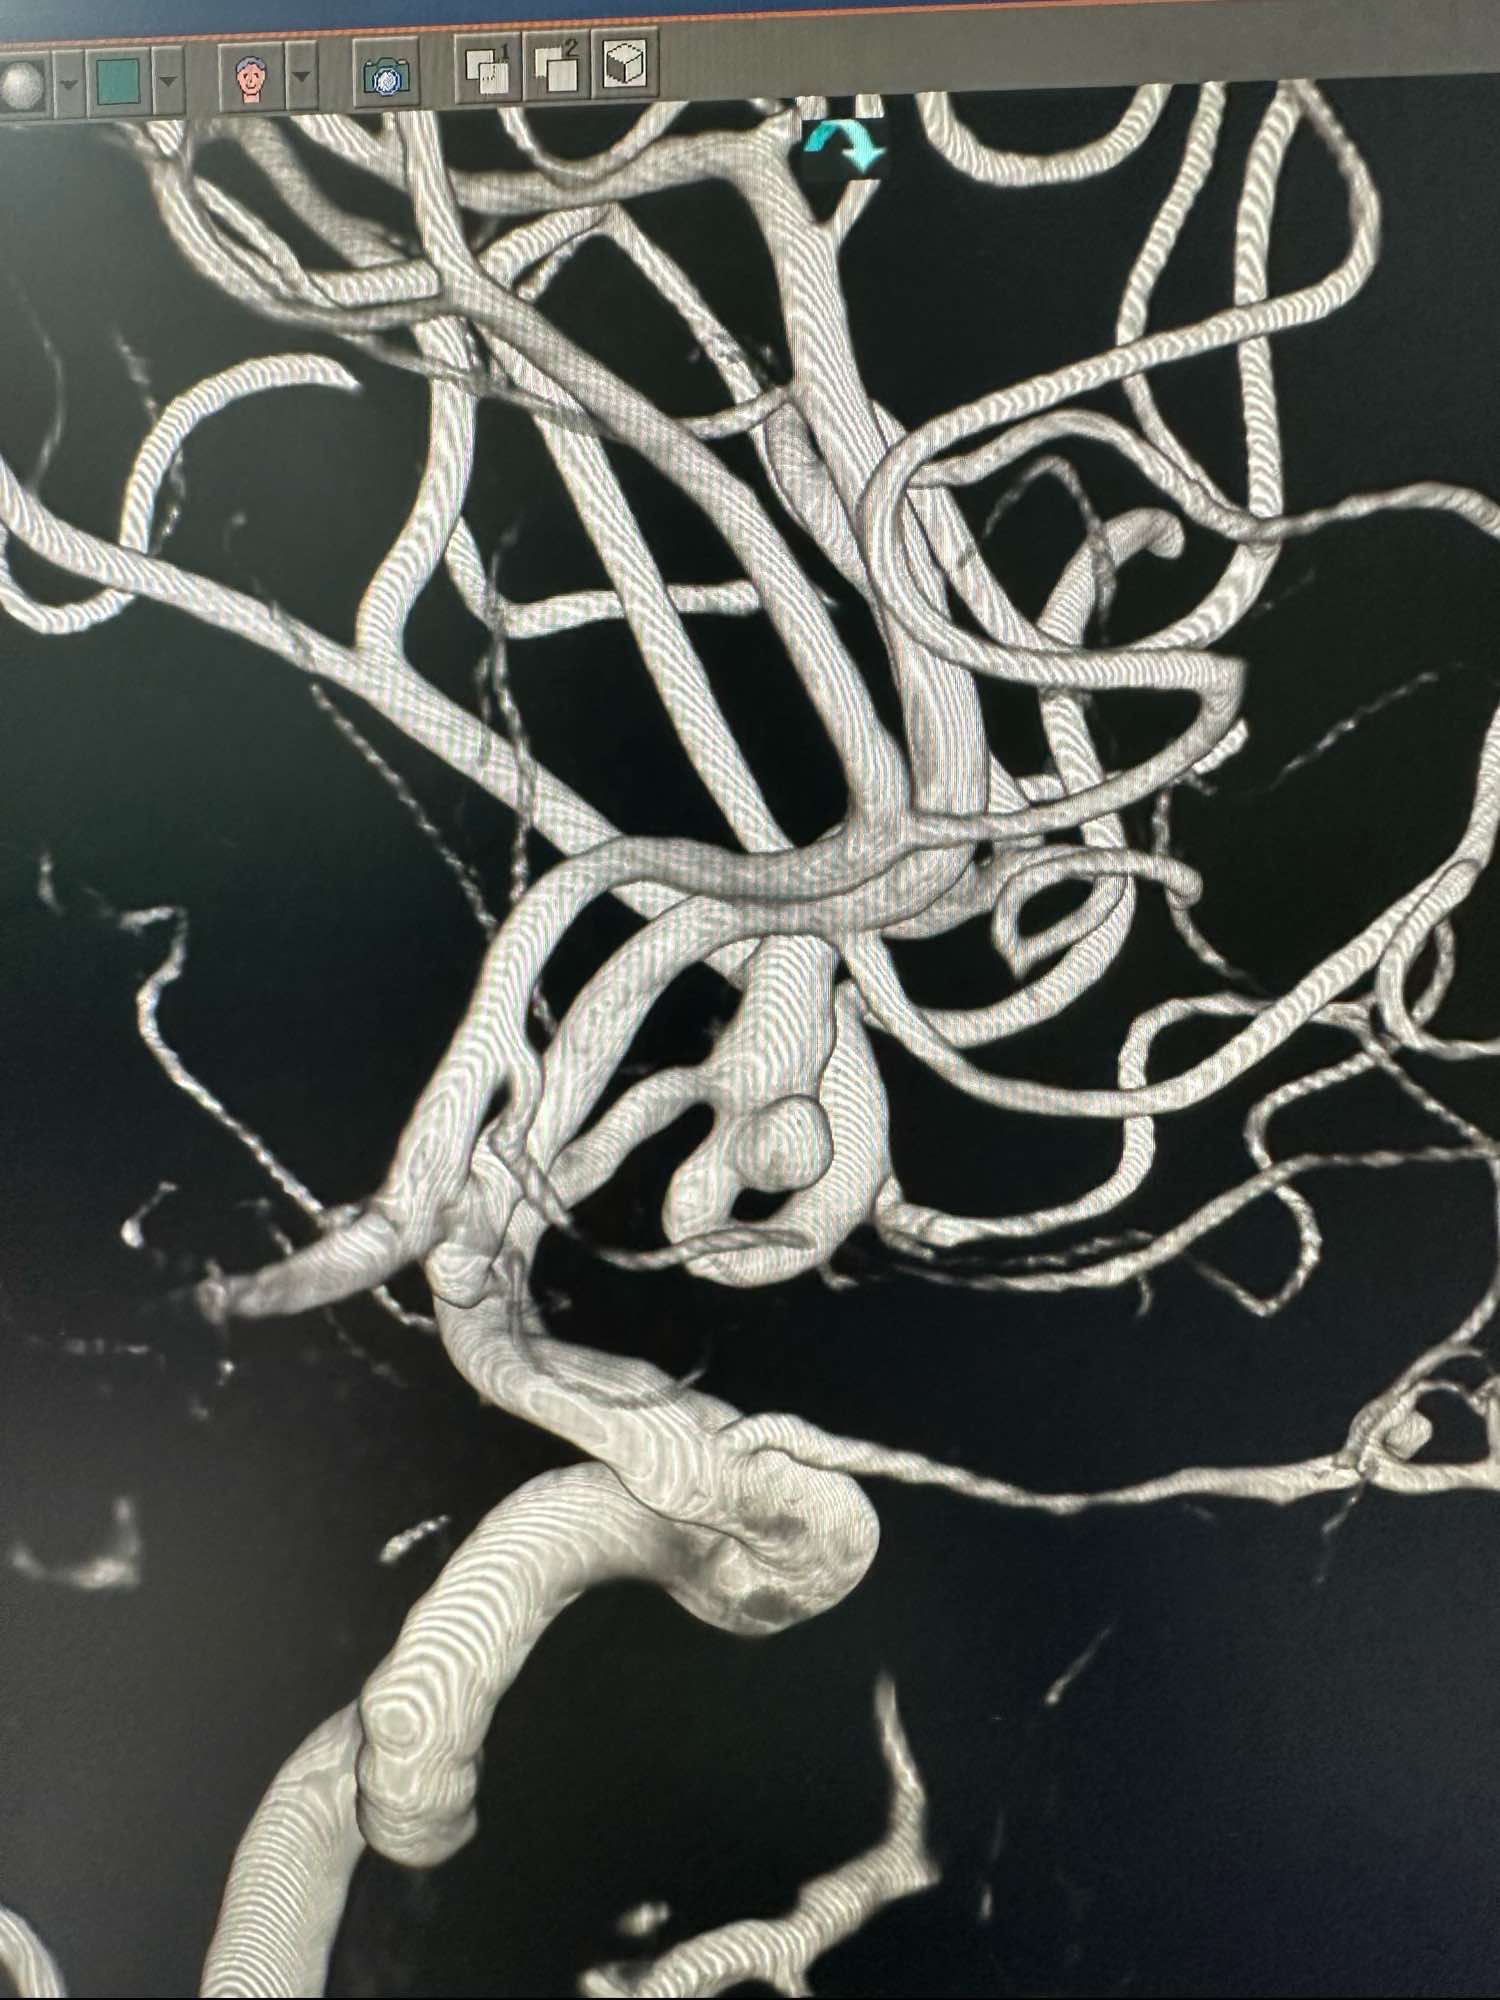

左侧颈内动脉术前3D图像

另外一个角度,动脉瘤大小约3mm左右,宽颈

另外一个角度